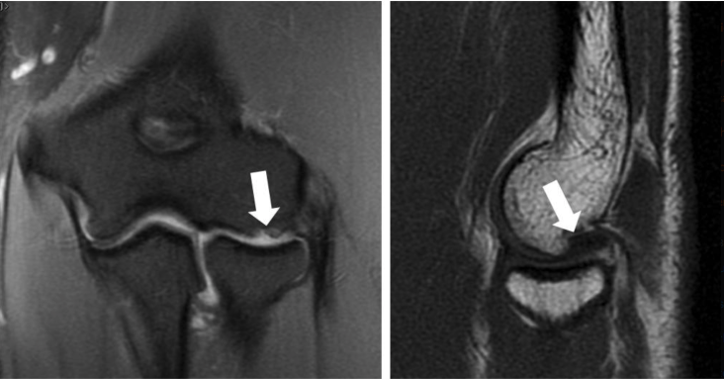

periosteal desmoid

Periosteal desmoid aka cortical desmoid aka distal femoral metaphyseal irregularity (many different names-yay). This is basically an avulsion injury 2/2 repeated microtrauma. Classic location is an eccentric cortical lucency in the medial femoral metaphysis. Usually young males, and commonly bilateral.